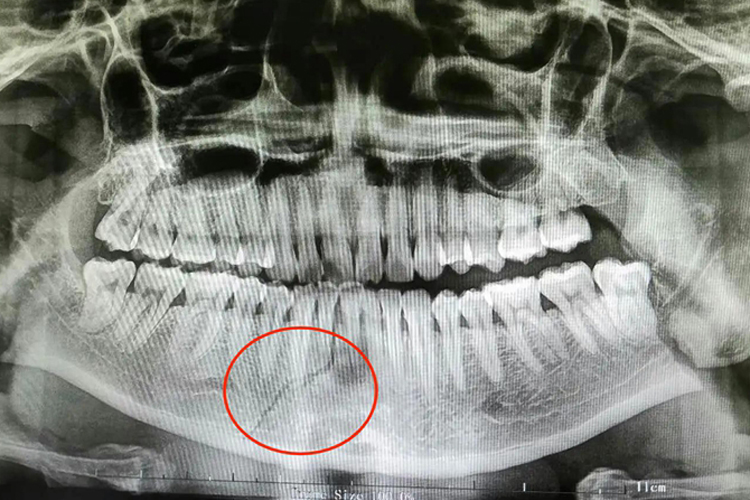

下颌骨骨折:骨折段易发生移位或者出现粉碎性骨折,撕裂邻近的牙龈和附着的黏膜,形成开放性骨折,易出现局部出血和肿胀,开口受限,可致使咀嚼、呼吸、吞咽、言语等功能障碍。